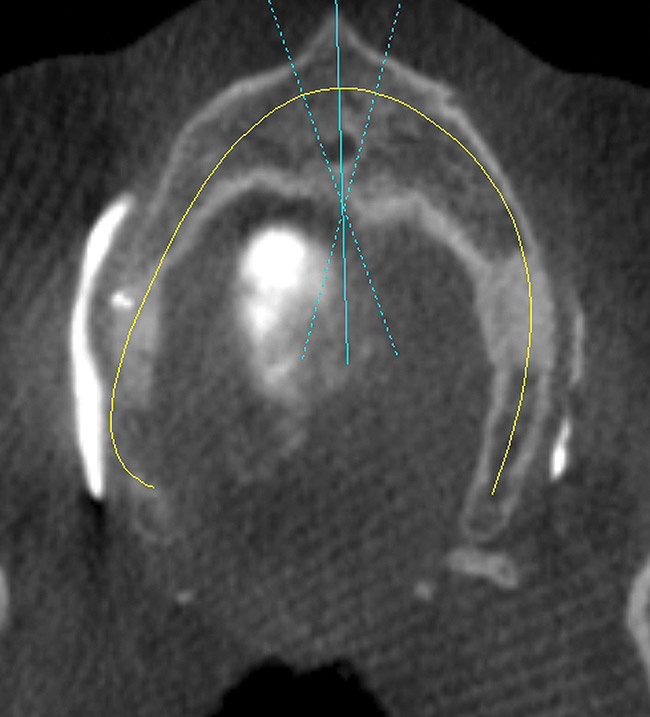

Figure 19   Panographic view 6 months post-graft showing substantial bone regeneration.

Figure 19

Figure 20  Panographic view of planning for implant placement.

Figure 20

After 6 months of healing, a CBCT scan was taken and good bone formation was seen on the axial (Figure 18) and panograph (Figure 19) views. The CBCT was then used to plan for placement of dental implants (Figure 20). Upon full-thickness reflection of the ridge, abundant bone contour was observed. Internal hex dental implants (BioHorizons) were placed according to the locations planned on the CBCT (Figure 21). After a healing period of 4 months, the implants were uncovered (Figure 22) and abutments were placed (Figure 23). A panograph taken 1 year after this stage revealed the final restorations on well-integrated implants (Figure 24). The patient’s smile reveals a fixed prosthesis that simulates her natural teeth (Figure 25).